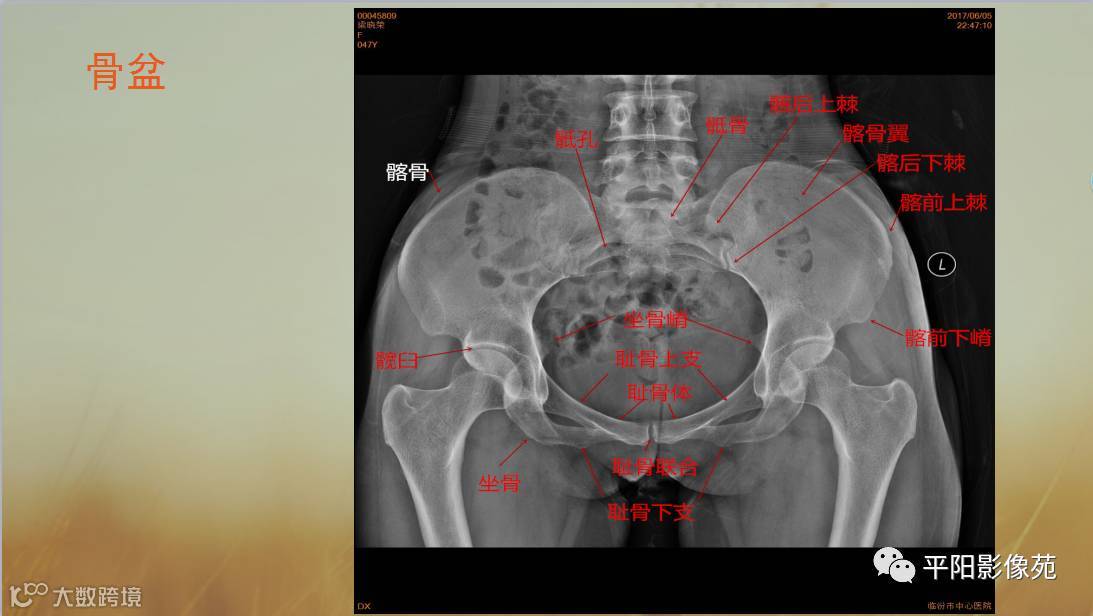

四肢骨骼X线解剖